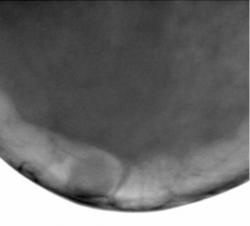

Протокол исследования. В левой молочной железе в верхнем наружном квадранте определяется снижение прозрачности железистого треугольника за счет избыточного развития фиброзной ткани, на фоне чего определяются очаговые уплотнения – по всей видимости, мелкие фиброаденомы. Аналогичные очаговые уплотнения в верхнем медиальном квадранте (1 – снимок в прямой проекции, 2 – снимок в боковой проекции). Передний контур железистого треугольника неровный. В верхнем наружном квадранте, на фоне премаммарного пространства определяется объёмное образование средней интенсивности, однородной структуры, с нечетким контуром, окруженное просветлением – «поясок безопасности», оттесняющее и сужающее молочный синус медиально. 3, 4 – участок, выделенный «навигатором» для более детального анализа патологического образования. 5 – для сравнения приведено обычное расположение молочного синуса.

5. для сравнения приведено обычное расположение молочного синуса.